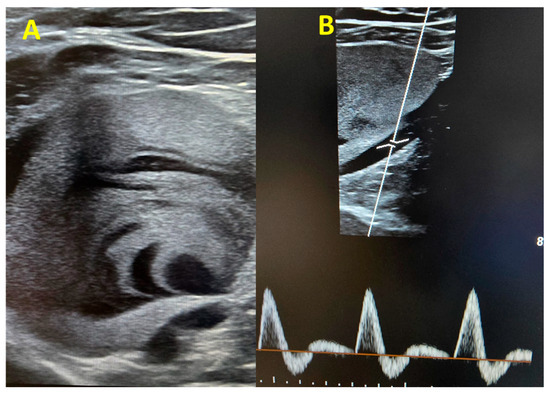

Within the following hours, a more comprehensive venous Doppler was performed, and we identified a large venous aneurysm in the upper left popliteal area (60/57 mm) with intracavitary thrombosis and intense contrast (Figure 2A). The popliteal artery showed normal caliber triphasic flux (Figure 2B), excluding the possibility of a popliteal artery aneurysm.

Figure 2. (A) Two-dimensional image of the popliteal vein aneurysm. Note the presence of the contrast and the partial thrombosis. (B) Normal Doppler PW flux in the popliteal artery.